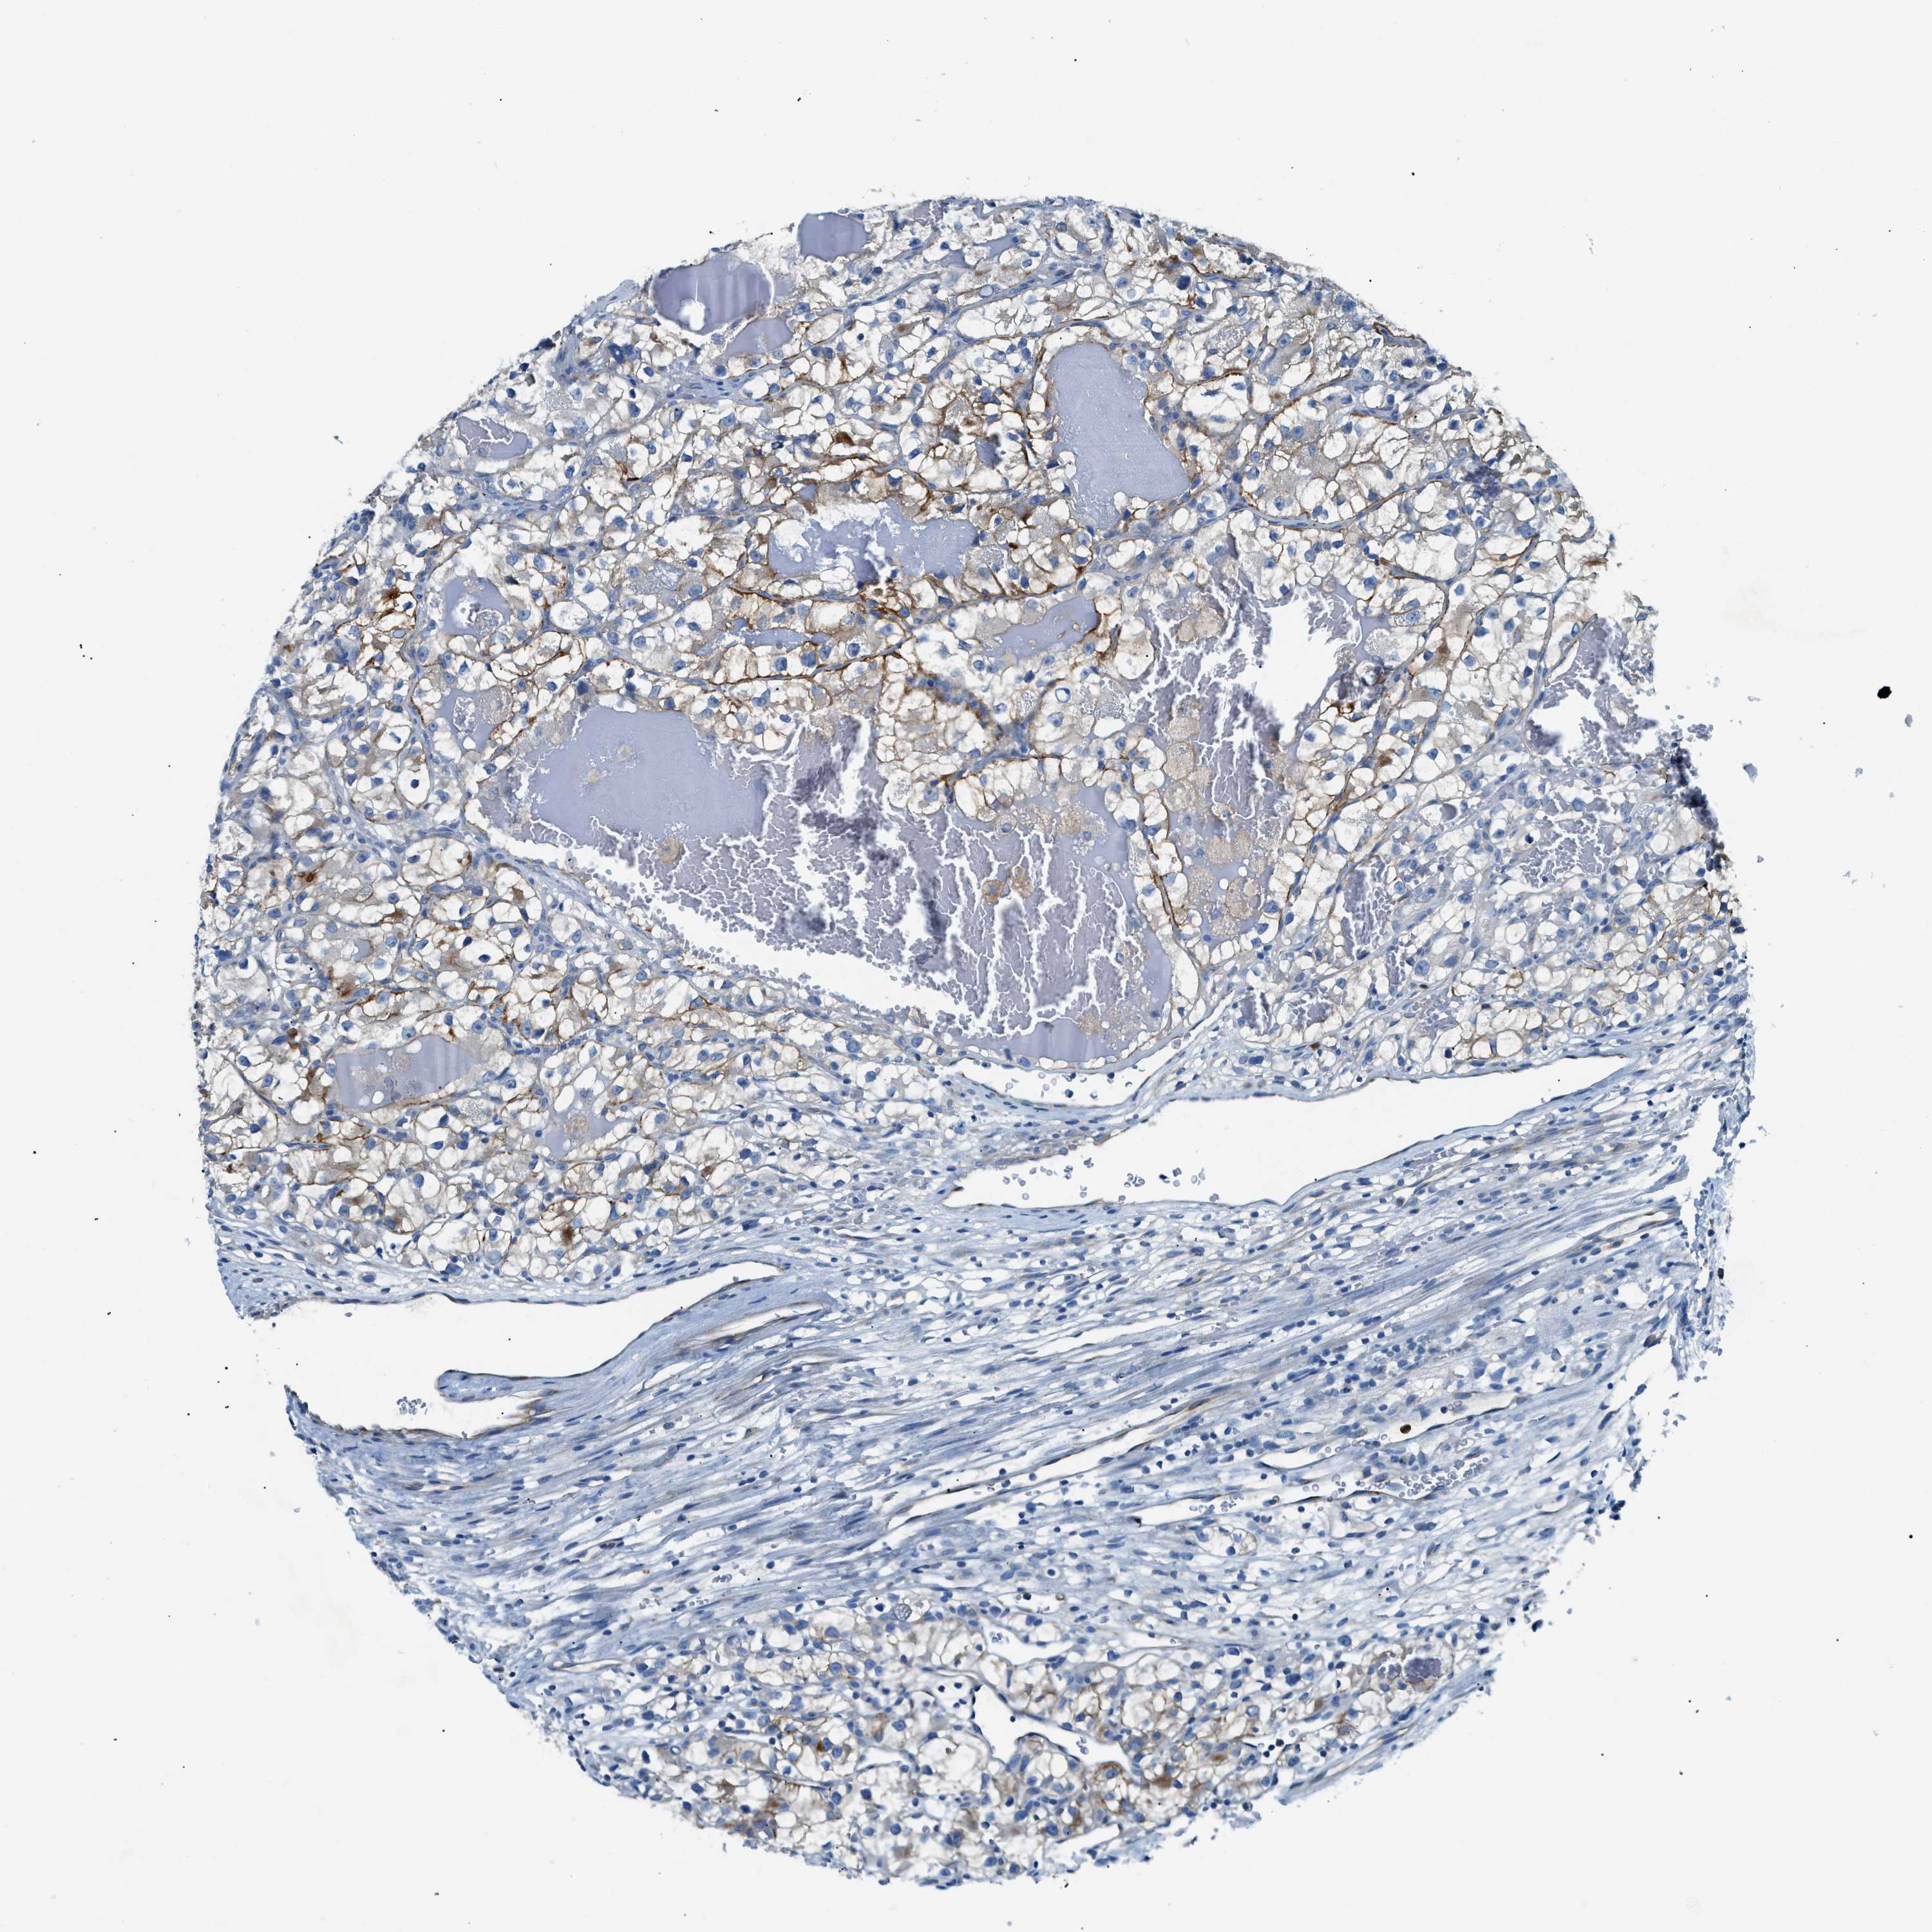

KIDNEY RENAL PAPILLARY CELL CARCINOMA (TCGA) - Interactive survival scatter ploti

The Survival Scatter plot shows the clinical status (i.e. dead or alive) for all individuals in the patient cohort, based on the same data that underlies the corresponding Kaplan-Meier plots. Patients that are alive at last time for follow-up are shown in blue and patients who have died during the study are shown in red.

The x-axis shows the expression levels (FPKM) of the investigated gene in the tumor tissue at the time of diagnosis. The y-axis shows the follow-up time after diagnosis (years). Both axes are complimented with kernel density curves demonstrating the data density over the axes. The top density plot shows the expression levels (FPKM) distribution among dead (red) and alive patients (blue). The right density plot shows the data density of the survived years of dead patients with high and low expression levels respectively, stratified using the cutoff indicated by the vertical dashed line through the Survival Scatter plot. This cutoff is automatically defined based on the FPKM cutoff that minimizes the p-score. The cutoff can be changed by dragging the vertical line or by entering a cutoff value in the square labeled "Current cut-off".

Under the Survival Scatter plot the p-score landscape (black curve; left axis) is shown together with dead median separation (red curve; right axis). Dead median separation is the difference in median mRNA expression between patients who have died with high and low expression, respectively. It is calculated as follows: median FPKM expression of dead patients with high expression - median FPKM expression of dead patients with low expression. This is intended to aid the user in visually exploring custom cutoffs and the associated p-scores and dead median separation.

Individual patient data is displayed and can be filtered by clicking on one or more of the category buttons on the top of the page. Categories describing expression level and patient information include: high, low, alive, dead, female, male and tumor stages. The scale of the x-axis can be toggled between linear and log-scale by clicking on the "x log" button. Mouse-over function shows TCGA ID, patient information and mRNA expression (FPKM) for each patient.

& Survival analysisi

Kaplan-Meier plots summarize results from analysis of correlation between mRNA expression level and patient survival. Patients were divided based on level of expression into one of the two groups "low" (under cut off) or "high" (over cut off). X-axis shows time for survival (years) and y-axis shows the probability of survival, where 1.0 corresponds to 100 percent.

ZDHHC13 is not prognostic in Kidney Renal Papillary Cell Carcinoma (TCGA)

Best expression cut offi